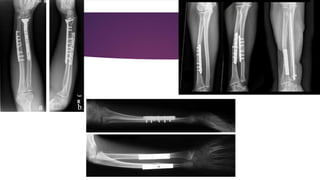

FRACTURES OF THE RADIUS AND ULNA

 Fractures of both bones of the forearm in adults are more difficult to treat compare to fractures in

children

 A direct injury usually produces transverse fractures at the same level

 Indirect injury, which almost always involves rotation, tends to produce oblique or spiral fractures at

different levels

 Because of the relationship between the radius and ulna during supination and pronation, both

fractures must be perfectly reduced in relation to alignment and rotation

 Open reduction is usually required for fractures of both bones of the forearm in adults, either as

primary or secondary treatment after failure of closed reduction

 The radius and ulna should be approached through separate incisions to minimize the risk of cross-

union between the two bones

 The most effective form of intemal fixation for these fractures is an AO compression plate and

screws

 The most often complication is malunion or even non union

FRACTURES OF THERADIUS AND ULNA  Fractures of both bones of the forearm in adults are more difficult to treat compare to fractures in children  A direct injury usually produces transverse fractures at the same level  Indirect injury, which almost always involves rotation, tends to produce oblique or spiral fractures at different levels  Because of the relationship between the radius and ulna during supination and pronation, both fractures must be perfectly reduced in relation to alignment and rotation

 Nevertheless, Sarmientorecommends treating fractures of both bones of the forearm by functional fracture-bracing (after 3 to 5 weeks in an above-elbow cast), the position of supination is satisfactory regardless of the level of the fractures  Open reduction is usually required for fractures of both bones of the forearm in adults, either as primary or secondary treatment after failure of closed reduction  The radius and ulna should be approached through separate incisions to minimize the risk of cross- union between the two bones  The most effective form of intemal fixation for these fractures is an AO compression plate and screws  The most often complication is malunion or even non union